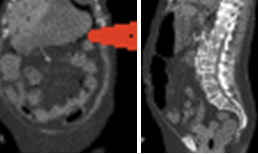

Resected obstructed ileal loop. Blue circles enclose the metastatic foci (Courtesy Dr. V. Penopoulos)

Red arrows — transition point. Multiple air-fluid levels (Courtesy Dr. V. Penopoulos)

The two metastatic foci causing stenosis and bowel obstruction are clearly visible (Courtesy Dr. V. Penopoulos)